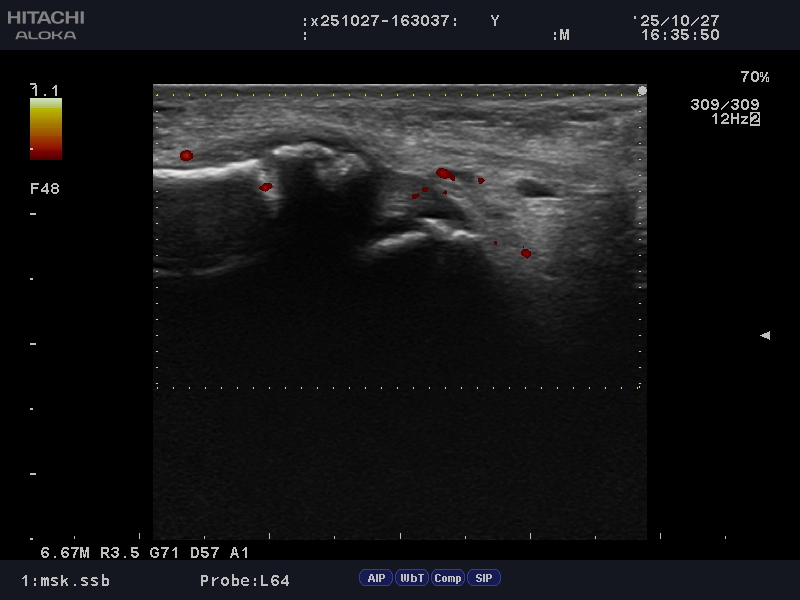

超音波検査にて遠位部に不正像を認めました。

下記参照

ドプラも腓骨部に反応